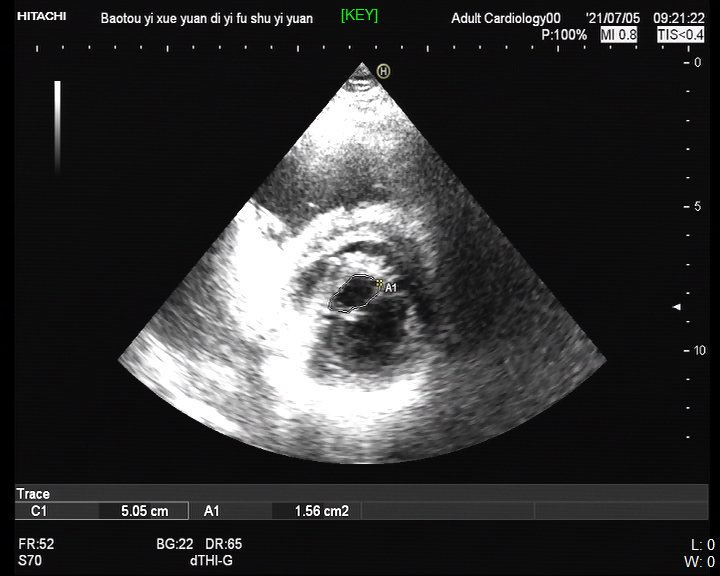

患者术前超声影像

专家建议外科换瓣治疗,但患者因惧怕开胸,一直未能手术。一月前,患者来到我院心内科裴汉军教授门诊就诊,心脏超声提示二尖瓣重度狭窄(二尖瓣瓣口面积0.9cm²),而主动脉瓣轻度狭窄目前无需干预,考虑到二尖瓣无严重钙化且活动度较好,瓣膜下结构无明显异常,左心房内无血栓形成,适合行经皮球囊二尖瓣扩张术。

手术如期进行,在局麻下将球囊导管从股静脉送至右心房,穿过房间隔进入左心房,顺血流方向跨越二尖瓣,用生理盐水和造影剂各半的混合液体充盈球囊,分离瓣膜交界处的粘连融合而扩大二尖瓣口面积,术后即刻瓣口面积增加至1.7cm²,患者症状和血流动力学迅速得到改善,术后6小时下床正常活动,手术取得圆满成功。